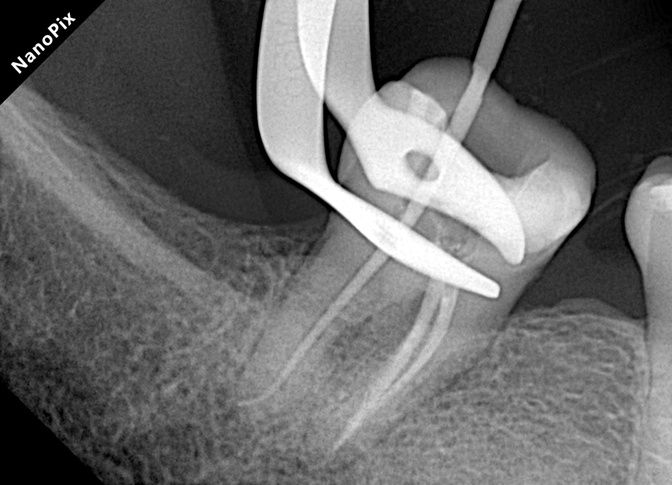

Paso 4 | Conformación

Instrumentación 3D hasta 35/.04 con el sistema Súper Flexi en todos los conductos. Se logró una conformación final amplia y conservadora, ideal para casos con necrosis pulpar y periodontitis apical.

✔️ Flexibilidad del sistema Súper Flexi: Permite alcanzar un calibre apical amplio (35/.04) sin alterar la anatomía original. Esta característica es especialmente valiosa en piezas con sobrecarga mecánica severa, ya que preserva la mayor cantidad posible de dentina pericervical y radicular, manteniendo la resistencia estructural del diente.